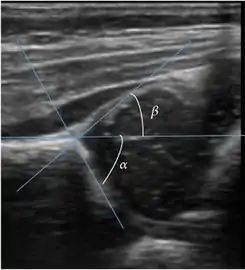

Ultrasound allows categorizing pediatric hips, according to Graf’s criteria, in four main types: normal, immature, and dysplastic (subluxed and dislocated). This classification is based on measurements of the acetabular inclination angle (alpha), cartilage roof angle (beta), and infant age. The femoral head coverage can also be determined by dividing the length of the femoral head covered by the acetabular fossa and the diameter of the femoral head. Its lower normal limits are 47% for boys and 44% for girls (Figure 11).[1]

Useful ultrasound measures in neonatal hip sonography, alpha and beta angles.[1]